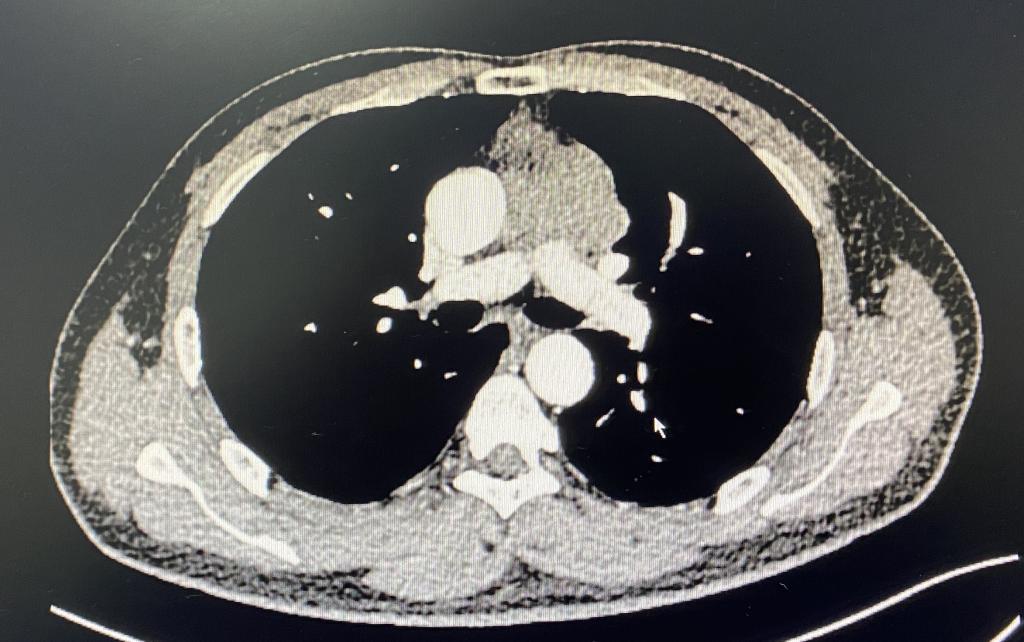

此位男性患者因声音嘶哑2月就诊,行胸部CT提示前纵膈可见不规则软组织密度,与主动脉弓、肺动脉主干和左肺上叶分界不清,大小约64mm x 18mm,于外院行穿刺活检示胸腺肿瘤,结合免疫组化考虑B型或AB型胸腺瘤。因手术难度大,肿瘤与周围重要组织和脏器关系密切,遂慕名转院来我院胸外科就诊。

病例1:术前胸部增强CT